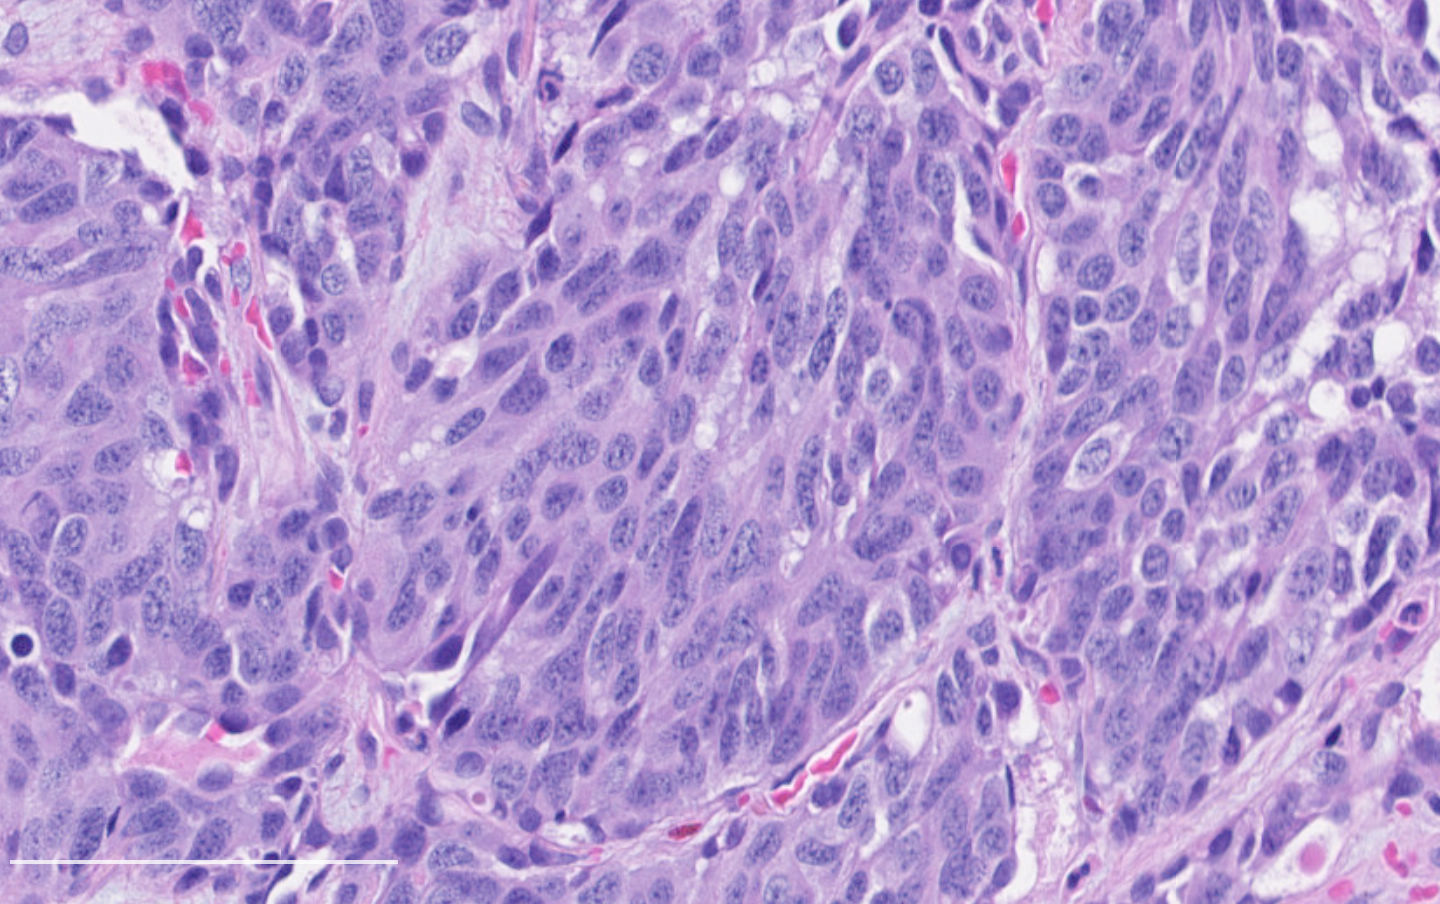

Contributed by Philippe Joubert, M.D., Ph.D.

- A patient undergoes a lobectomy for a well circumscribed nodule. On H&E slide, the tumor exhibits a well differentiated neuroendocrine morphology and you observe the histologic features presented in the image. Which of the following statements is true?

B. It is defined as a well differentiated neuroendocrine tumor with 2 - 10 mitoses per 2 mm² or foci of necrosis. The picture shows a carcinoid lung tumor with a classical neuroendocrine morphology and 2 mitoses in 1 high power field. Even though the whole tumor is not presented here, the presence of 2 mitoses is sufficient for an atypical carcinoid diagnosis.

While Ki67 proliferation rate is frequently > 10% in atypical carcinoids, this feature is not part of the diagnosis (A). C is nearly exact but mitotic count is not made on 1 high power field. Finally, the diagnosis can be suggested on small samples but a thorough examination of a resection specimen is necessary to confirm an atypical carcinoid diagnosis (D).